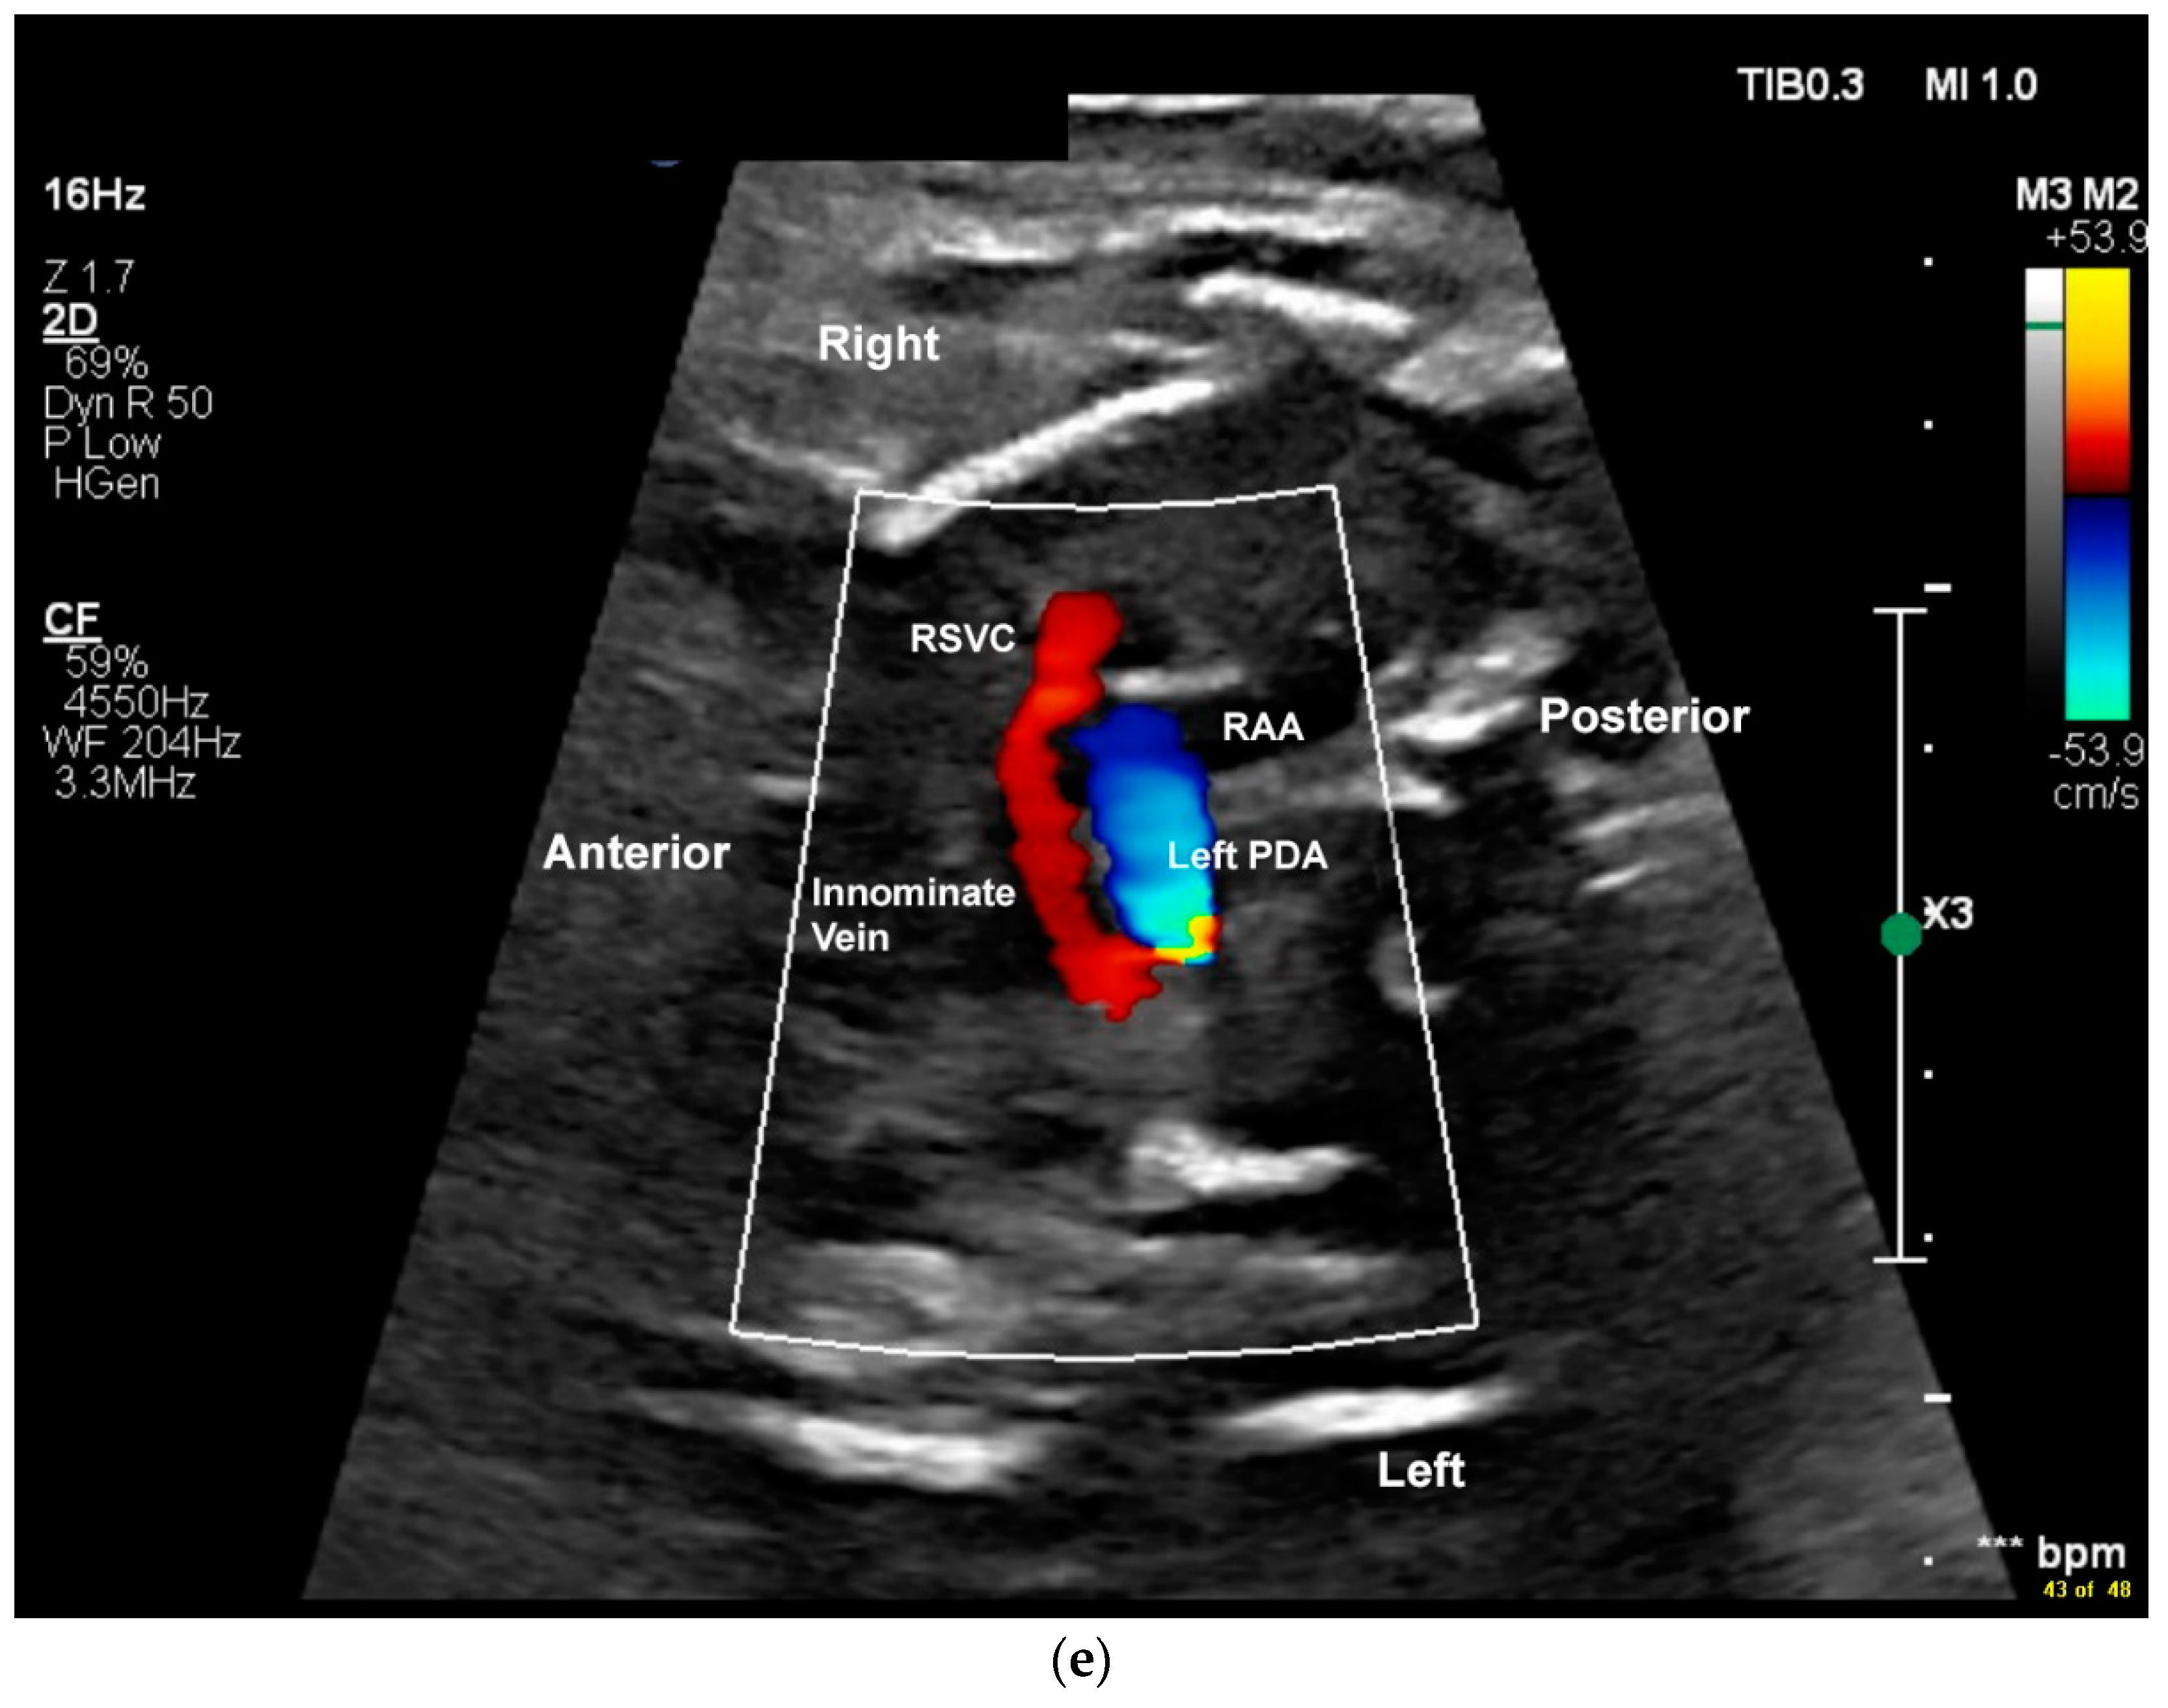

2.2. Case 2